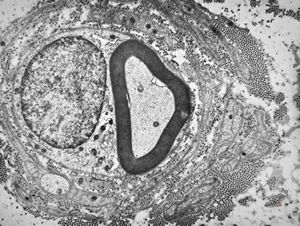

![F,23y. | n.suralis - hypertrophic demyelinating neuropathy [onion bulb] F,23y. | n.suralis - hypertrophic demyelinating neuropathy [onion bulb]](../img/OGDEM/015 Soft tissues/0076.jpg)

F,23y. | n.suralis - hypertrophic demyelinating neuropathy [onion bulb]

![F,23y. | n.suralis - hypertrophic demyelinating neuropathy [onion bulb] F,23y. | n.suralis - hypertrophic demyelinating neuropathy [onion bulb]](../img/OGDEM/015 Soft tissues/0077.jpg)

F,31y. | hypertrophic demyelinating neuropathy - n.suralis

M,13y. | n. suralis - hypertrophic demyelinating neuropathy